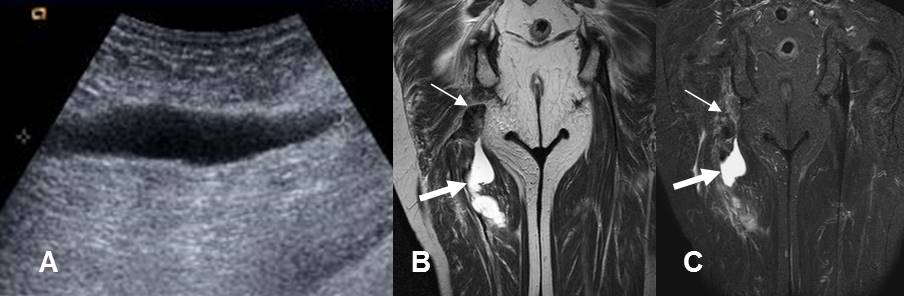

Fig 152. Ruptura muscular.

A: Ecografía longitudinal. Colección líquida, que corresponde a hematoma.

B: RM coronal en T2 y C: RM coronal en STIR. Ruptura en el origen de los isquiotibiales, con extremo retraído. (Flechas delgadas). Existe hematoma intermuscular asociado. (Flecha gruesas).